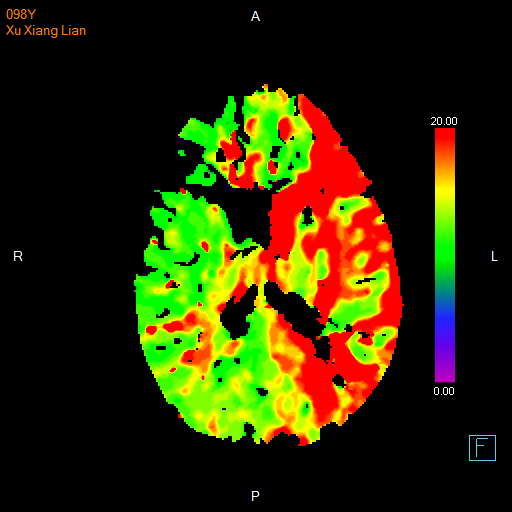

进一步的血管检查(CTA+CTP)发现了更严重的问题:王奶奶的左侧颈内动脉完全闭塞——这是脑梗中最凶险的类型之一,意味着大脑主要供血通道被切断,随时可能危及生命

颅脑 CTP